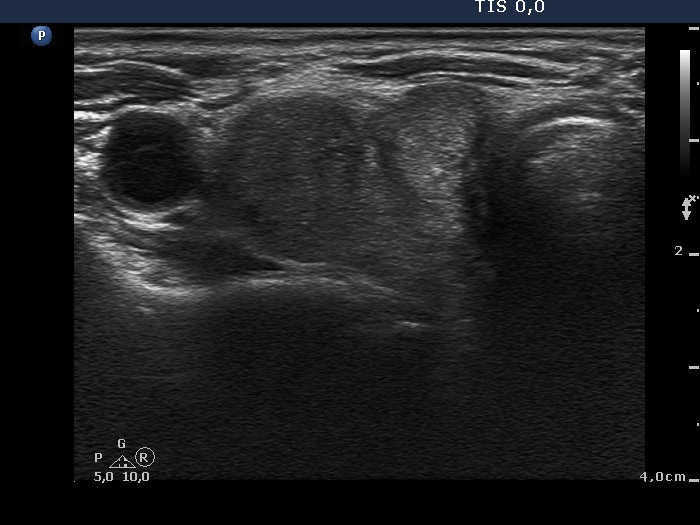

Ultrasonography: the thyroids were moderately hypoechogenic and contained several discrete, circumscribed lesions. There was a hyperechogenic nodule in the lower part of the right lobe while a cystic nodule in the upper part of the left lobe.

The thyroid is hypoechogenic and is surrounded with a relatively thin echonormal rim. This makes an appearance if both lobes were composed of a large hypoechogenic nodule. However, the echonormal rim corresponds to thickened connective tissue; a frequent phenomenon in an operated thyroid.

The upper part of the right lobe seems to be nodular, i.e. composed of two nodules at first sight. However, an insertion of the connective tissue and an acoustic shadow of a coarse calcification divides this part of the thyroid to two lesions. These do not fit nodules in a pathological sense.